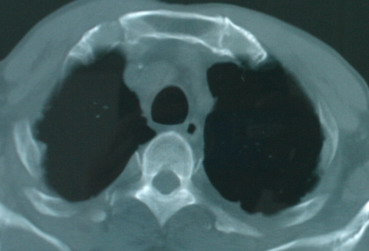

以下是引用卜一在2008-6-3 19:33:00的发言:[br]双肺结节,以双上肺分布为多,期间搀杂片状致密影及索条致密影。考虑:继发性肺结核伴血型播散可能性大。不除外肺泡ca的可能!另:椎体退变!

以下是引用panyishengct在2008-6-3 21:09:00的发言:[br]双上肺弥漫性小结节影,纵隔窗内钙化淋巴结影,考虑矽肺或/和tb可能性较大,不除外肺ca可能。腰椎考虑退变。 [br][br]